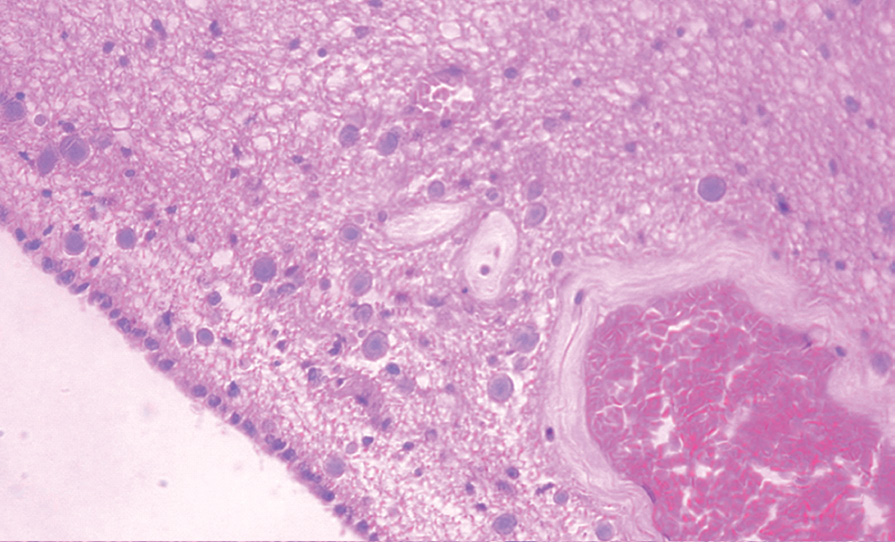

В старческом возрасте в мозолистом теле превалируют микроглиоциты среднего диаметра, образующие между собой крупные скопления. Следует заметить, что в данной возрастной группе также выявлены и микроглиоциты крупного диаметра (более 20 мкм), входящие в состав скоплений. Скопления микроглиоцитов наиболее часто просматриваются возле сосудов, в то время как в толще ткани мозолистого тела для них характерно обособленное расположение (рисунки 1, 2).

Рисунок 2. Фрагмент мозолистого тела женщины 71 года. Скопления микроглиоцитов разного диаметра возле сосуда. Окраска гематоксилином и эозином. Увеличение 100.

В ткани мозолистого тела возрастные нейродегенеративные изменения выражены более явно. Так, к старческому возрасту в местах скоплений микроглиоцитов отмечается значительное снижение экспрессии нейрофиламентов с формированием участков их разрежения (рисунки 3, 4).

Рисунок 4. Фрагмент мозолистого тела мужчины 72 лет. Скопления микроглиоцитов разного диаметра вблизи сосуда. Экспрессия белка нейрофиламентов снижена в местах скоплений микроглиоцитов. Увеличение 100.

В мозолистом теле человека в первом периоде зрелого возраста наблюдаются отдаленные друг от друга микроглиоциты, как правило, мелкого (иногда среднего) диаметра. К старческому возрасту динамика возрастных параметров микроглиоцитов в мозолистом теле выражается в статистически достоверном увеличении их количества и суммарного диаметра за счет преобладания микроглиоцитов среднего диаметра и появления единичных микроглиоцитов крупного диаметра, входящих в состав крупных скоплений вблизи сосудов.

Экспрессия нейрофиламентов в ткани коры предцентральной извилины головного мозга как в первом периоде зрелого возраста, так и в старческом возрасте равномерная. Наряду с этим в ткани мозолистого тела общая тенденция возрастной динамики заключается в значительном снижении экспрессии нейрофиламентов в местах скоплений микроглиоцитов и появлением участков их разрежения к старческому возрасту.